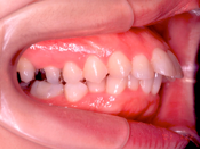

1) 主訴 上の歯が出ており、口が閉じにくい 発音が悪い

2) 診断名 上顎前突

3) 初診時年齢 15歳

5) 抜歯 左右上顎第一小臼歯、下顎左右下顎第二小臼歯(計4本)

6) 治療期間 開始時から装置装着まで3か月、マルチブラケット期間2年3か月、保定期間4年